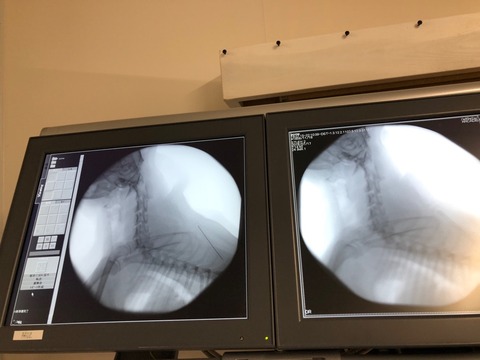

このポメ君は 先日のレスキューで来た子です、

呼吸が ゼイゼイ ヒューヒュー言って苦しそうでした、昨夜 ゴールデンを八匹降ろしていたら

先生が来てくださって 診察をして下さったのです。

結果は 気管虚脱で した、苦しそうだからなるべく早くに手術をしましょうと、、、

急遽今日の夜 都合をつけて手術に来てくださる事になりました。